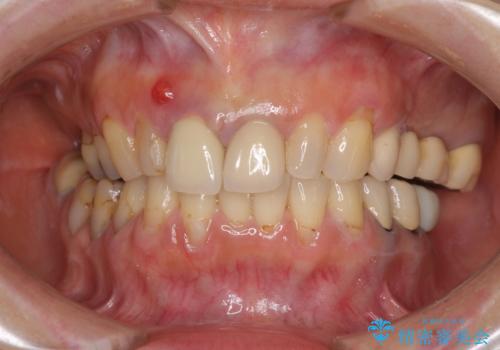

- 神経の抜いた歯が折れてしまい、痛みを感じて来院された患者様です。

折れてしまった歯は抜歯せざるを得ないため、抜歯と同時に仮歯を装着し、その後オールセラミックブリッジにて補綴することとしました。

折れた前歯を抜歯すると、歯肉が痩せてしまい、ブリッジの形態の審美性が失われることがあります。仮歯を調整することで審美回復が必要であるか判断しますが、今回は歯肉移植を行うことなく補綴治療を行いました。